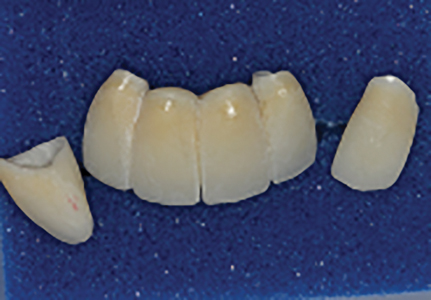

Bis-bake for try-in

Immediate insert